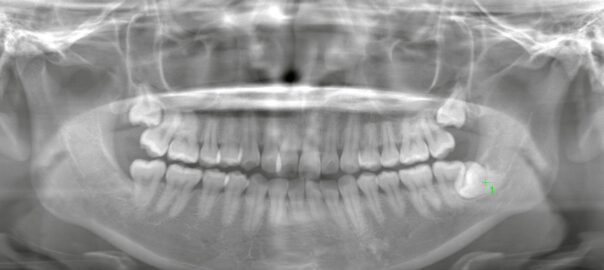

歯根が直角に湾曲した埋伏親知らず|2Dレントゲンでは見えないリスクとは?

こんにちは。東京都中央区銀座5丁目にある 【親知らず・顎関節症クリニック銀座(通称:オヤアゴクリニック)】です。 当院は以下の3つに特化した歯科クリニックです。 * 親知らずの抜歯 * 顎関節症の治療 * アスリートのた … 続きを読む 歯根が直角に湾曲した埋伏親知らず|2Dレントゲンでは見えないリスクとは?